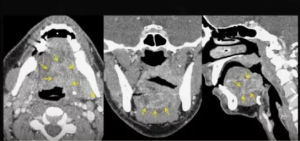

На рис. 1 и 2 иллюстрируется инвазия плоскоклеточной карциномы в скелетные и собственные мышцы языка при МРТ и МСКТ с контрастированием пациентки А., 57 лет, и пациента Х., 61 лет, в двух ортогональных плоскостях: аксиальной и корональной.

По результатам проведенного исследования корректное определение распространенности рака языка с помощью МСКТ и МРТ, включая оценку глубины инвазии и вовлечение мышц языка (собственных и скелетных), было классифицировано как истинно положительные результаты, которые составили 36 (67,9%) случаев по данным МСКТ-исследования и 41 (77,4%) случай по данным МРТ-исследования. Истинно отрицательными (ИО) считались результаты, при которых были даны заключения об отсутствии инвазивного роста ПКР, подтвержденные патоморфологическим исследованием. ИО-результаты по данным МСКТ- и МРТ-исследований были выявлены в 10 (18,9%) и 8 (15,1%) случаях соответственно.